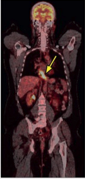

PET Scan

The distal esophagus was intensely FDG avid Pet scanning (SUV 6.2).

The lymph node was also intensely FDG avid (SUV 8.3)